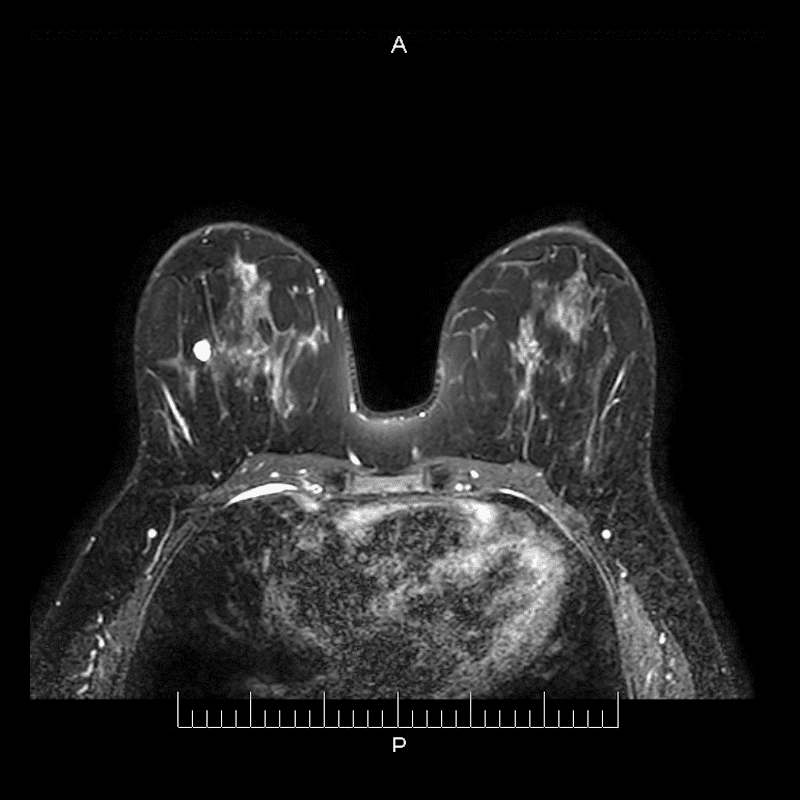

La paciente se recuesta sobre la mesa del equipo RM, ambos senos son posicionados sobre una antena especial, la cual adquiere las imágenes.

Primero se toman imágenes sin la sustancia de contraste.

Una inyección intravenosa de sustancia de contraste (gadolinio) se aplica a la paciente.

Se adquieren las imágenes de perfusión (con contraste).

Ambas imágenes son comparadas.